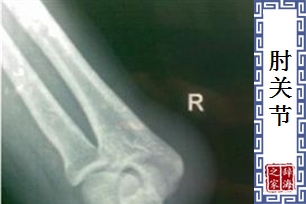

- 连接肱骨与前臂骨的关节。

- 解剖学名词。前臂骨和上臂骨(肱骨)之间的关节。其结构上由 肱骨和尺骨之间的屈戍关节; 尺骨和桡骨之间的车轴关节; 肱骨和桡骨之间的球关节等形成。共同包着关节囊。内外侧分别为内侧侧韧带,和外侧侧韧带做为补强。